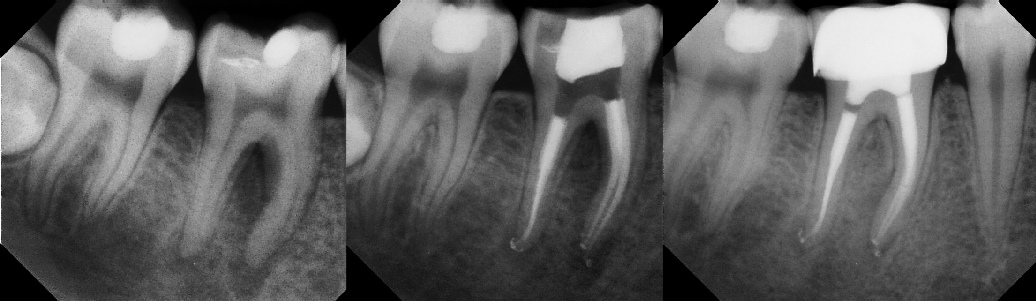

COMPLICATED ANATOMY LARGE LESIONS CALCIFIED CANALS PERFORATION / RESORPTION SEPARATED INSTRUMENTS SURGICAL CASES RETREATMENT / pOST REMOVAL OPEN APICES ACCESS THRU CROWNS Root Canal Case Portfolio

Pre-op Post-op 6 mos.